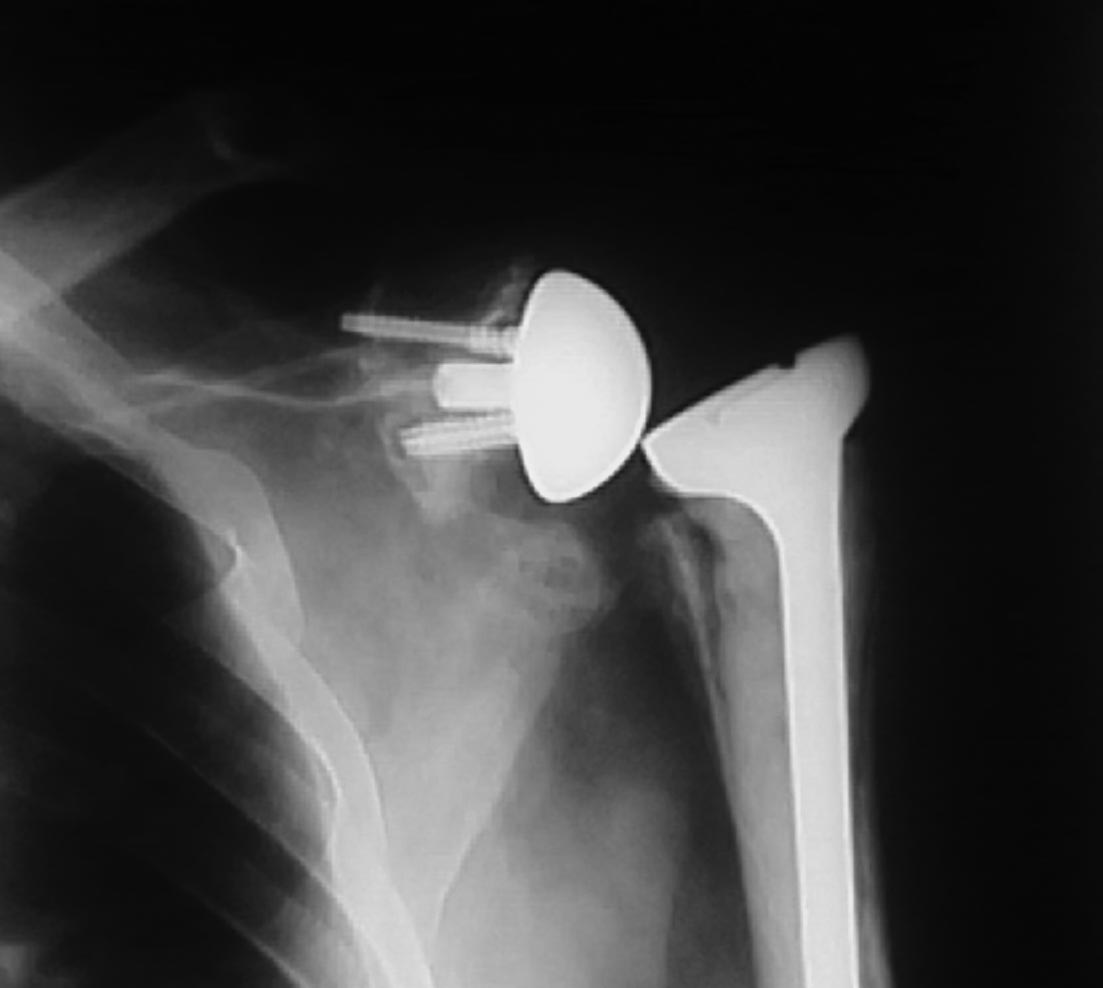

Мужчина 56 лет,после реэндопротезирования по поводу асептического некроза головки плечевой кости,обратился на приём с жалобами на ограничение движений в плечевом суставе,вот какую рентгенологическую картину я увидела.

Здравствуйте!Установлен эндопротез De puy delta.

По тому, как ситуация представлена - без каких-либо вопросов - можно только согласиться, что да, на снимке вывих эндопротеза.

Желательно дополнить Rhg в аксиальной проекции (в идеале КТ). Есть подозрение на "нестабильность" гленоидального компонента, вплоть до перелома по уровню шейки лопатки. А вывих может быть связан c "Нуч"-конфликтом при приведении конечности.